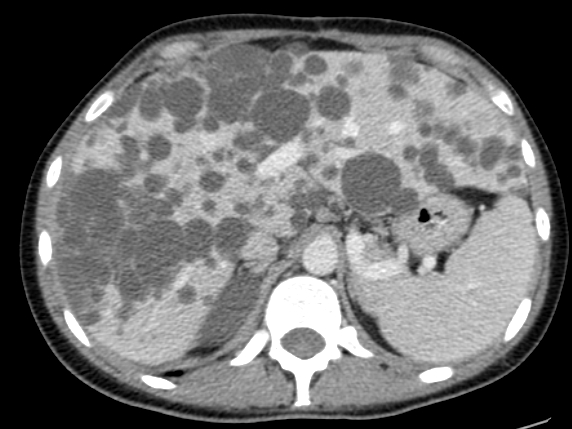

Enfermedad poliquística

La presencia de quistes hepáticos múltiples puede ser un indicador de la enfermedad poliquística del adulto, la cual tiene un carácter autosómico dominante en su patrón hereditario. Esta condición puede manifestarse con la formación de quistes no solo en el hígado sino también en los riñones, siendo conocida como poliquistosis renal cuando ambas están presentes.

Con el transcurso del tiempo y el aumento en el número y tamaño de los quistes, estos pueden volverse palpables durante la exploración física. En estudios de imagen como la ecografía, los quistes hepáticos aparecen como estructuras llenas de líquido, sin ecos internos, a menos que ocurra sangrado o infección.

En la ecografía, una herramienta diagnóstica habitual para quistes hepáticos, se observan varios quistes llenos de líquido, sin ecos internos, a menos que se presenten complicaciones como sangrado o infección.